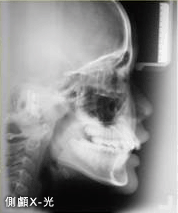

- 矯正治療開始前,

- 要進行一些簡單的常規檢查與記錄,了解口腔與牙齒的情況:

- b. 全口及側顱X光檢查。